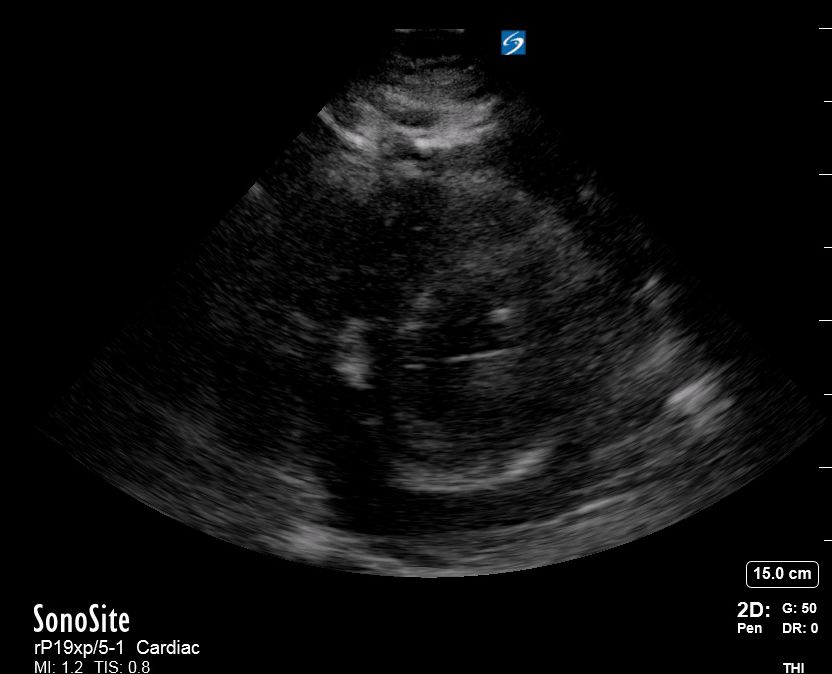

THE VIEWS

The PLAX view is versatile and allows the recognition of multiple landmarks, making it good for visual estimation of LV contractility. It is essential to optimize the view ensuring a true sagittal long axis, as being oblique to the LV chamber may underestimate its size and overestimate its emptying. The PSAX view at the level of the papillary muscles reveals the entire muscular circumference and concentric squeeze of the LV. It is useful to estimate both global function and focal wall motion abnormalities. The A4C view, although technically challenging, provides good insight into the global myocardial function and chamber size.

LV CONTRACTILITY

Qualitative assessment of the LV and visual estimation of Ejection Fraction is based on three parameters:

Endocardial excursion.

Myocardial thickening.

Movement of the anterior leaflet of the mitral valve.

A qualitative assessment is typically categorised as:

Normal (LVEF 50-65%)

Moderately Depressed (LVEF 30-50%)

Severely Depressed (LVEF < 30%)

Hyperdynamic (LVEF > 65%)

SIGNIFICANTLY IMPAIRED / DILATED LV

A severely depressed LV contractility, particularly when paired with a plethoric IVC or lung B-lines, indicates systolic heart failure. Chronically raised afterload can lead to severe dilation of the LV.